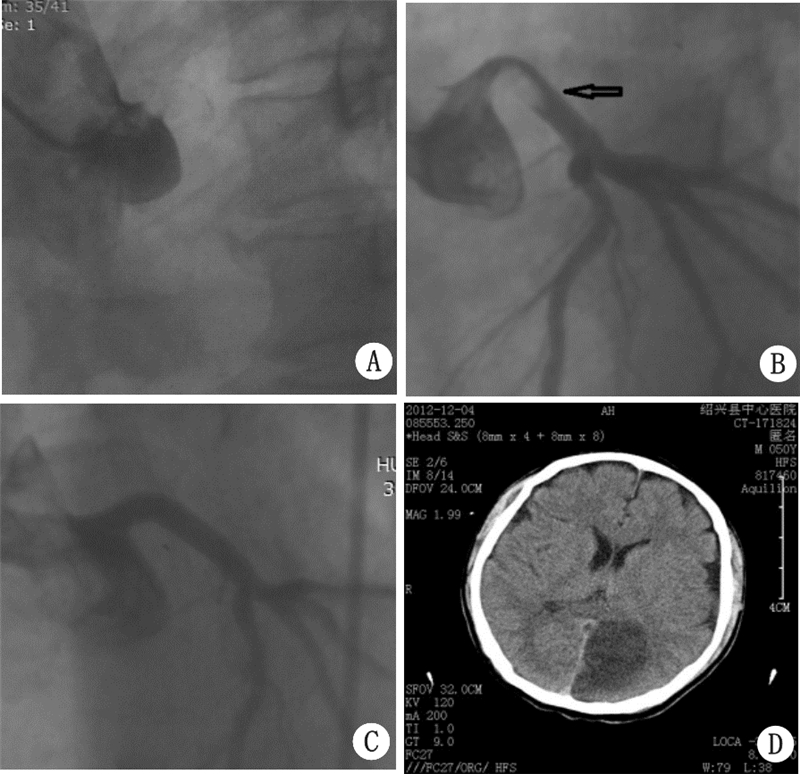

患者男性,50岁,因“胸痛2 h”入院于2012年11月30日。2 h前在活动时出现胸前区疼痛,显持续性,伴头晕,出汗,无恶心、呕吐等,急呼120送当地中医院,当时查心电图示急性前壁心肌梗死,予以口服阿司匹林、氢氯吡格雷片各300 mg后,转送本院。有20年喝酒及抽烟史。烟约每日1包,酒每日500 mL。否认有高血压病、糖尿病、心脏病及脑梗死病史,从事体力劳动;否认家属中有类似病史。入院查体:T 35.0 ℃,P 102次/min,R 33次/min,BP 96/58 mmHg(1 mmHg=0.133 kPa),意识尚清,精神软弱,口唇轻度发绀,两肺呼吸音对称,未及干湿性啰音,心率102次/min,律不齐,闻及早搏,约5次/min,未及杂音,腹平软,肝脾肋下未触及,两下肢浮肿阴性,神经系统未见阳性体征。考虑:急性广泛前壁心肌梗死。同家属商量后,决定行急诊PCI术,术中所见:右冠未见明显狭窄,左主干开口后全闭(图 1A),决定行左冠PCI术。顺利通过导丝到前降支远端,重复造影显示左主干开口巨大血栓,送入抽吸导管抽出红色血栓,后重复造影示左主干近端仍见血栓,但血栓随着造影剂返流逸出冠脉口(图 1BC),进入主动脉,冠脉血流恢复通畅,未见明显狭窄,术中出现恶性心律失常,反复除颤16次,并持续胸外按摩近30 min,予以机械呼吸,因血压偏低,术中予以IABP植入,于入院第4天在减少镇静剂用量时,发现有烦躁,查病理征阴性,为排除脑血管意外可能,行头颅CT检查示左顶枕叶脑梗(图 1D)。住院半个月,顺利康复出院。

A:左主干全闭;B:左主干内可能巨大血栓;C:血栓被造影剂冲出后冠脉正常;D:头颅CT示顶枕叶脑梗 图 1 患者造影及CT结果